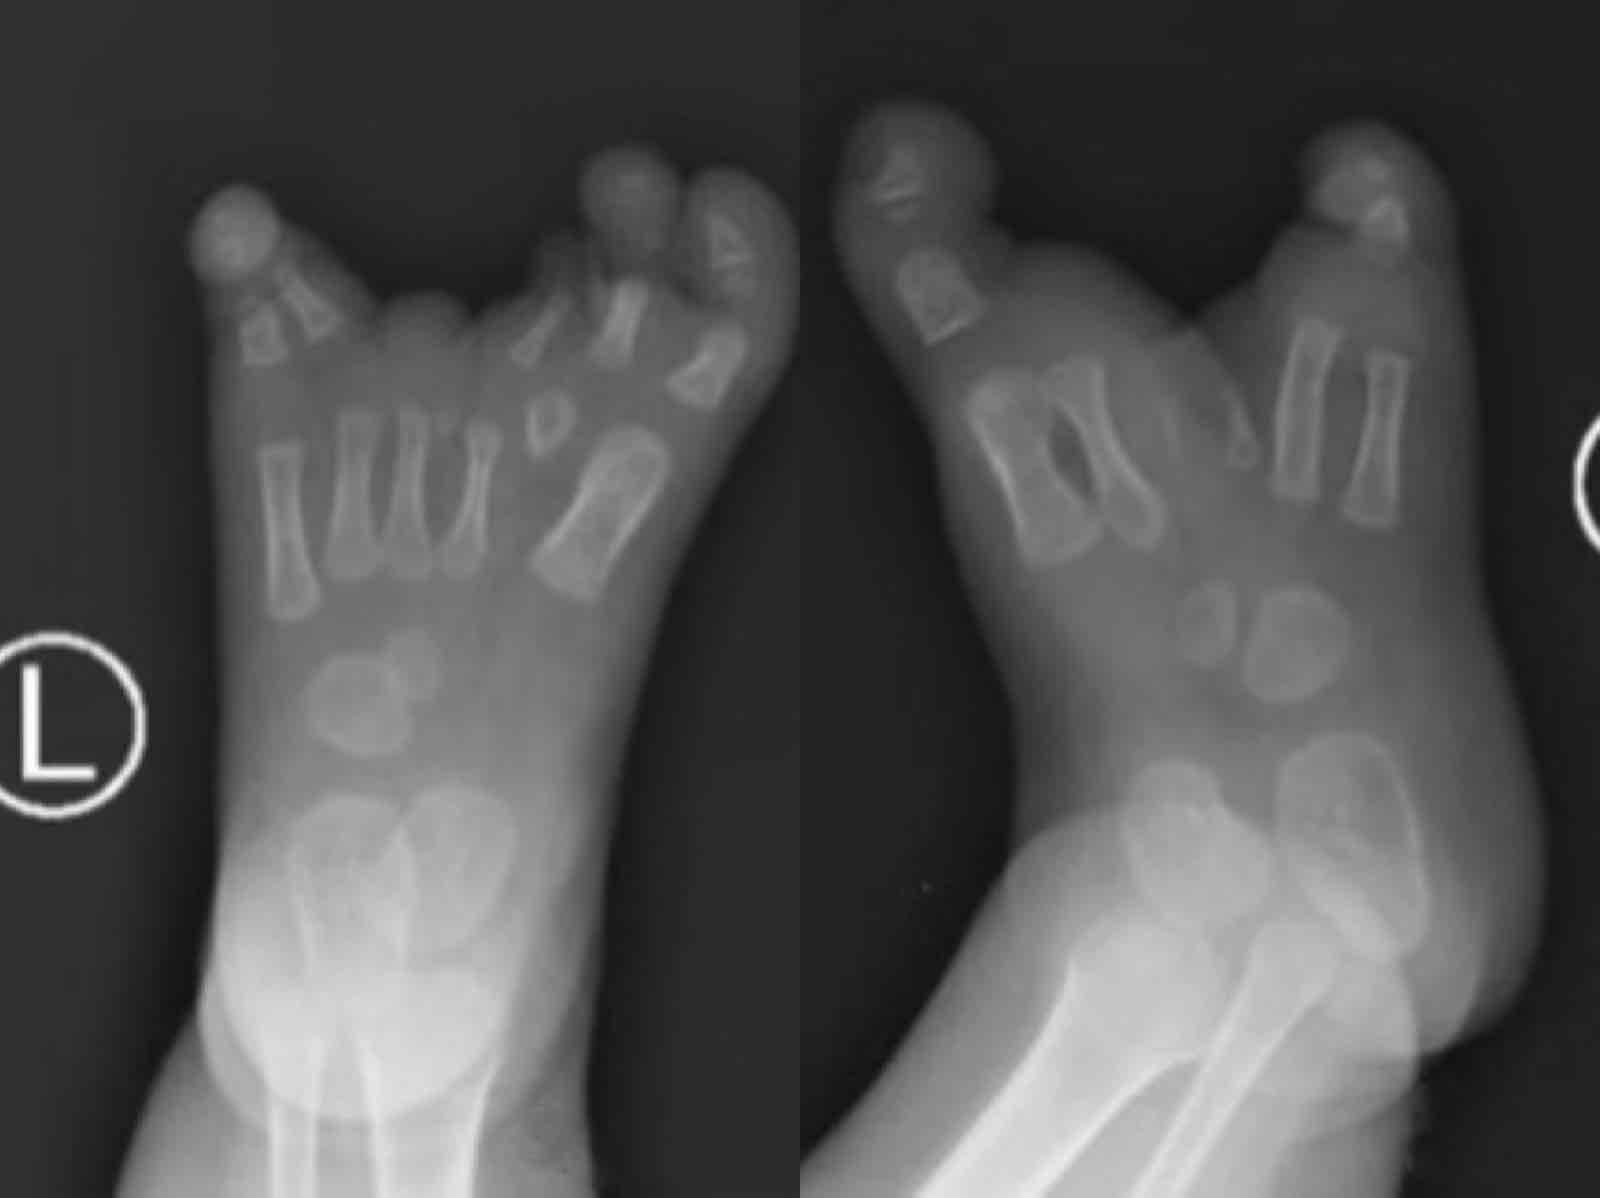

她的右脚只有大脚趾和小脚趾,中间的脚趾头是残缺的。左脚的情况也没有好多少:左脚有三根脚趾,而且除了大脚趾,其他两根脚趾头都是畸形的。

靓靓的脚看上去像是从中间裂开了,“V型”的裂口越来越大,大脚趾和其他脚趾分别指向两边。这不仅没法穿袜子、穿鞋,也影响了正常学站立、走路。

原来,靓靓得的这个“怪病”,在医学上称为先天性裂足。这是一种罕见的畸形,又称“龙虾爪”或先天性缺趾畸形。

深圳市儿童医院骨二科主任韩镜明介绍,这个病是在胎儿期由于四肢端骨的正中轴发育异常,引起余趾发生不同类型的缺失或融合。患儿如没有及时治疗,对他们的肢端功能及生活将有严重的影响。